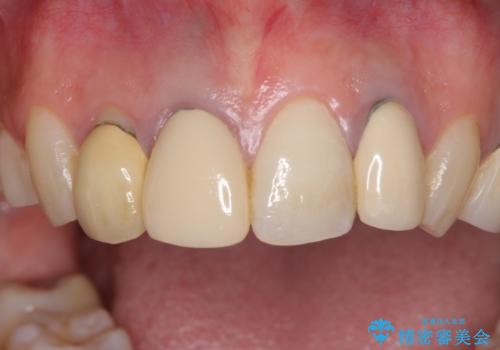

- 以前治療した前歯のクラウンの色が気になるとのことで来院された患者様です。

3歯別々に治療したクラウンは、どれも未治療の前歯を異なる色調で、口元が縞模様の印象でした。

更に、土台やフレームの金属色により、歯肉ラインが黒ずんでしまっていました。